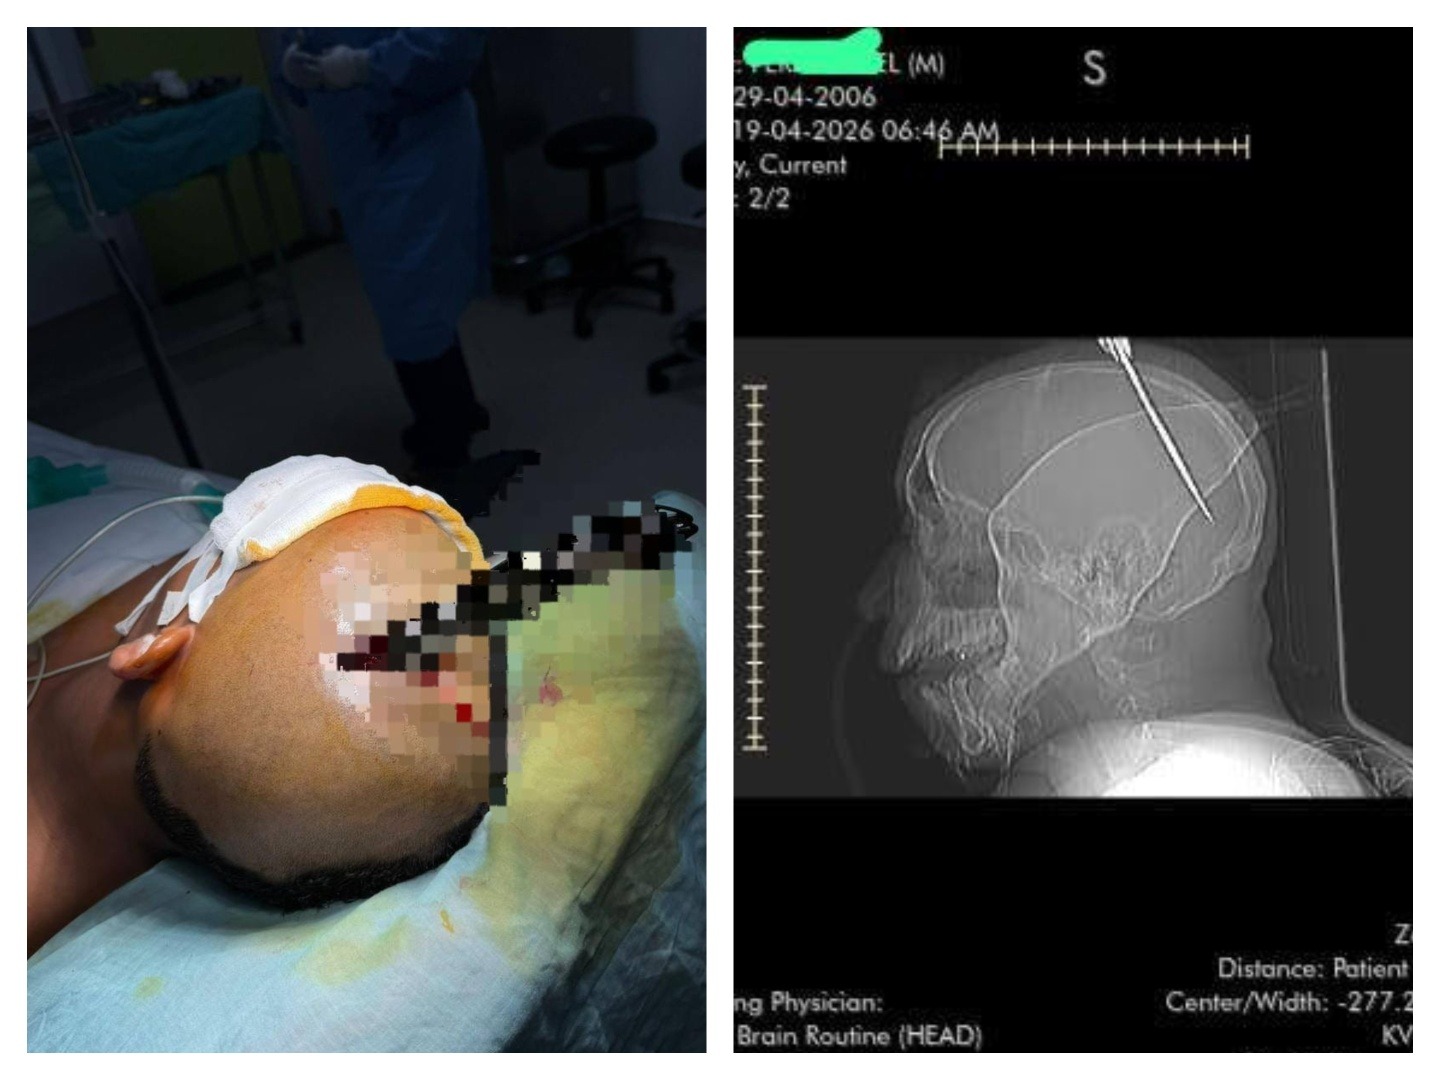

A Cuban national, 19 years old male, was rushed to the hospital’s emergency room after sustaining a violent stab wound to the head during an altercation at a social gathering.

Upon arrival, he presented with a knife deeply embedded in his skull—a rare and highly dangerous form of penetrating brain injury. Such cases are exceptionally critical, as any movement of the object can result in catastrophic bleeding, irreversible brain damage, and death.

Recognizing the urgency, the on-call neurosurgical team mobilized immediately. Within minutes, the patient was stabilized, and advanced imaging was performed to assess the blade’s trajectory and depth. The scans revealed that the knife had penetrated the cranial vault and entered the brain, lacerating tissues in the speech center of the brain with active intracranial bleeding.

The surgical team performed a carefully planned procedure to safely remove the foreign object. Unlike routine trauma cases, extracting an embedded knife from the brain requires meticulous control to prevent secondary injury. The surrounding bone and cerebral tissues were exposed, and the blade was removed in a controlled manner, minimizing bleeding and preserving neurological function.